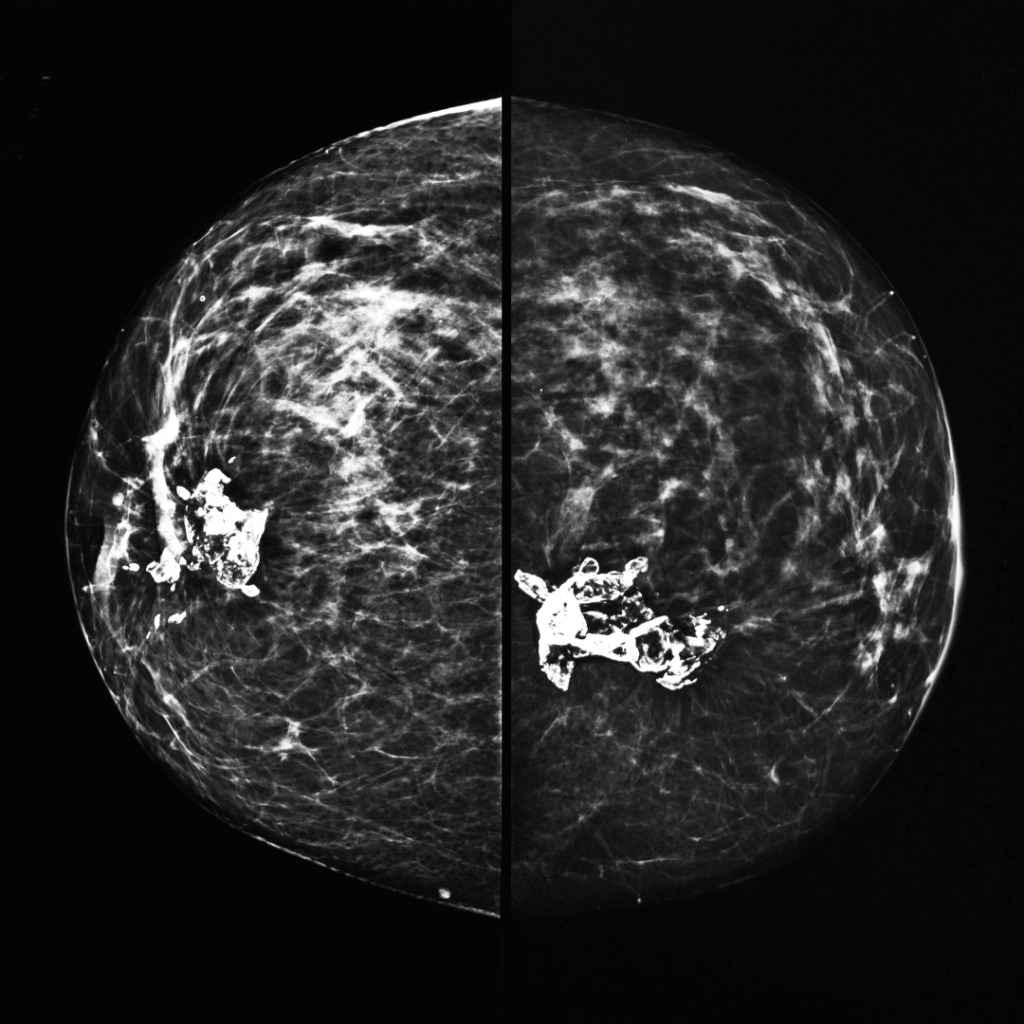

Mammography is a specialized breast imaging test that uses low-dose X-rays to detect early signs of breast cancer.

Digital mammography captures images electronically, allowing radiologists to zoom, adjust contrast, and evaluate breast tissue more accurately—especially in women with dense breasts. It is currently considered the gold standard for breast cancer screening worldwide.

• Multiple views (like CC and MLO) are taken for complete evaluation.